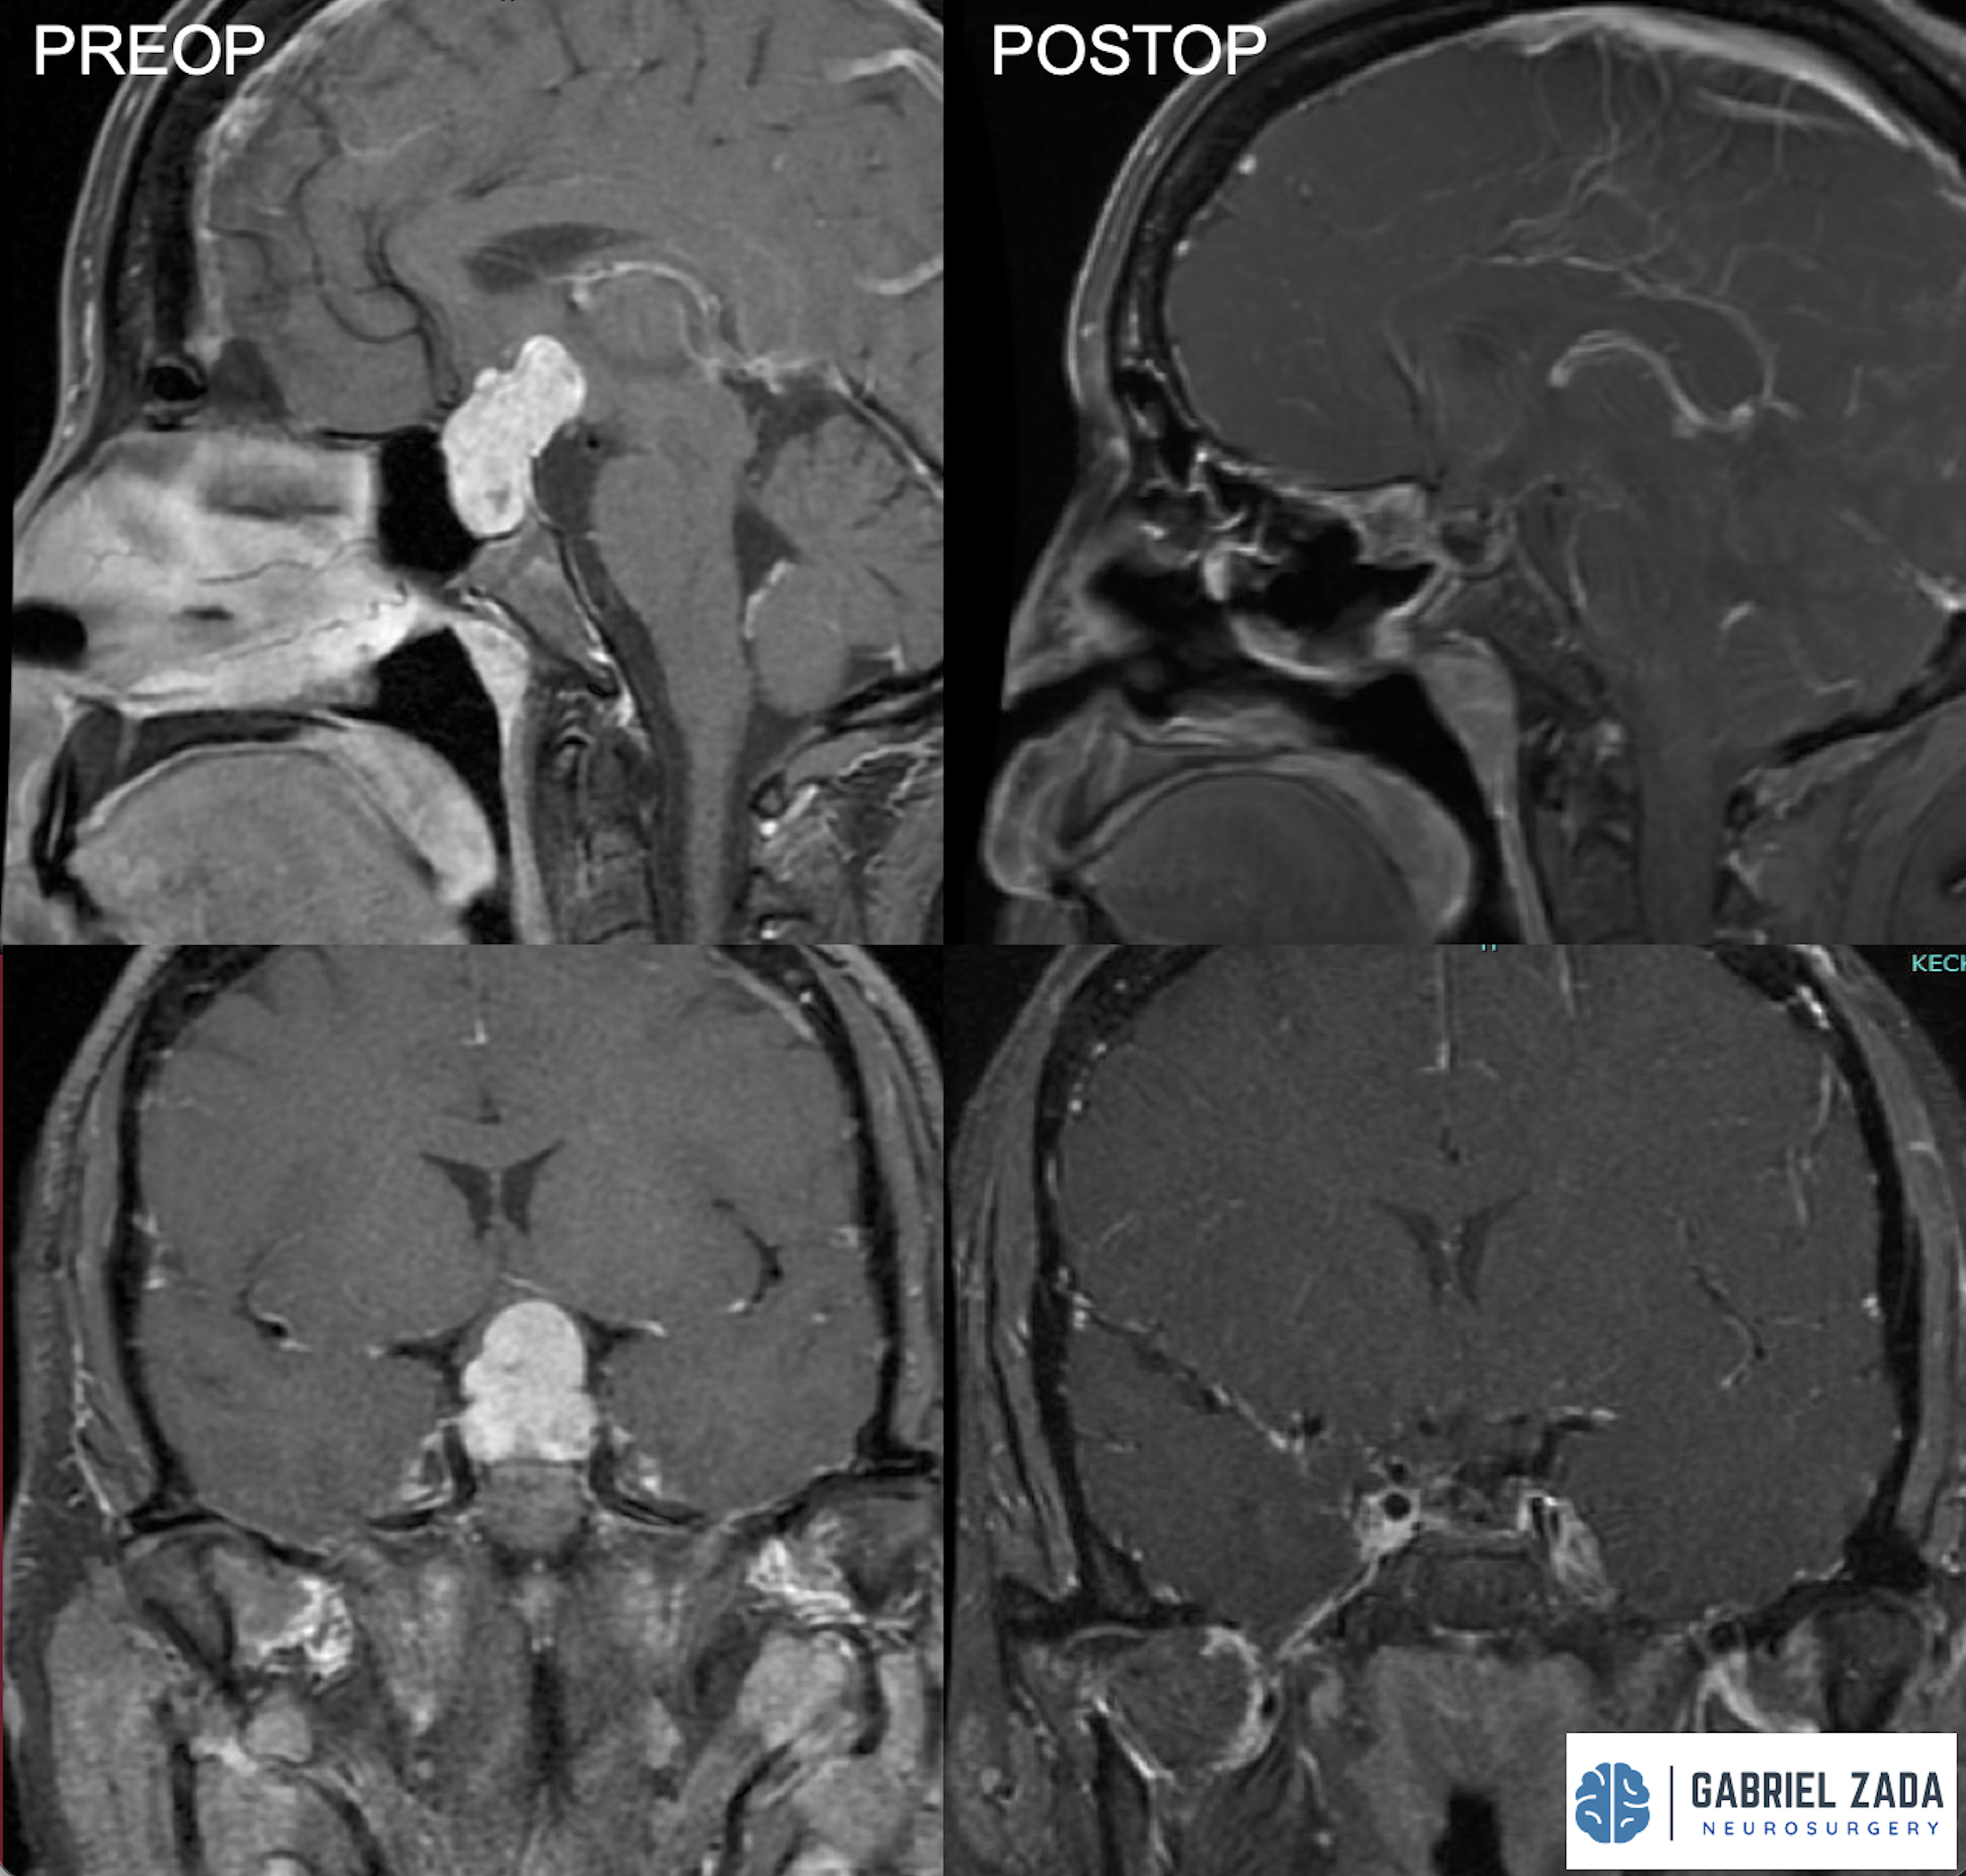

Explore this comprehensive gallery featuring pre‑ and post‑operative imaging of patients with skull‑base tumors treated by Gabriel Zada, MD, MS, FAANS, FACS. These cases highlight Dr. Zada’s expertise in advanced neurosurgical techniques and outcomes.

*Representative cases shown for educational purposes. All images de-identified. Individual results vary.